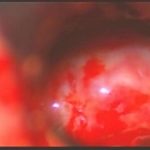

術中写真

摘出 中